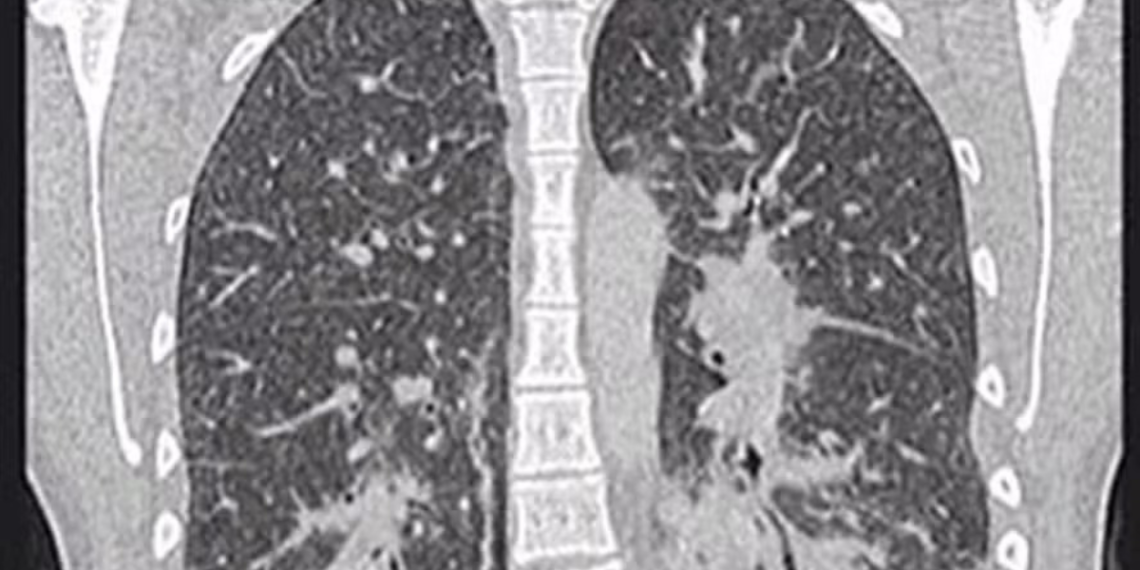

O diagnóstico do “pulmão de pipoca” é clínico e envolve exames como tomografia de tórax e espirometria. Como a doença pode ser confundida com asma ou DPOC (Doença Pulmonar Obstrutiva Crônica), é comum haver atraso no diagnóstico.